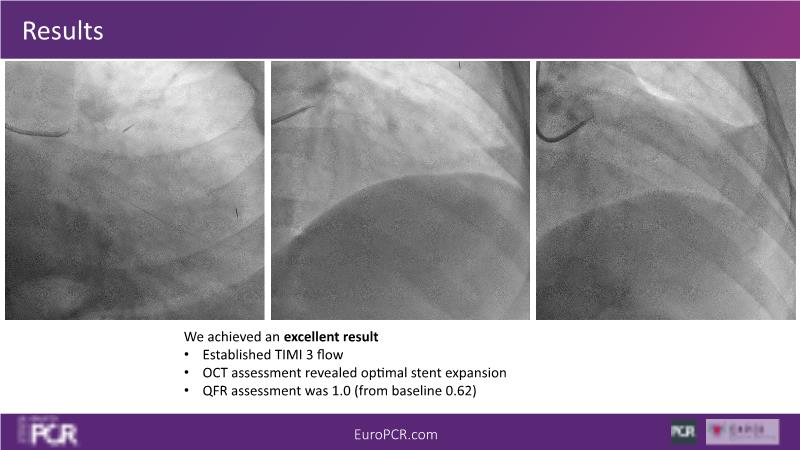

Join this session to delve into the unmet needs concerning drug-eluting stents (DES), including poor long-term clinical outcomes, with up to a 50% MACE rate at 10 years, and a non-plateauing 2-3% annual event rate. Explore how DynamX Bioadaptor technology addresses these challenges by maintaining the established flow lumen and restoring hemodynamic modulation of the artery. Discover the sustained clinical benefits demonstrated in a 2-year RCT, potentially establishing a new treatment standard for CAD patients. Gain insights into patient types benefiting most in clinical practice, such as those at higher risk of restenosis (e.g., LAD disease, long lesions, small vessels, co-morbidities), and younger patients with longer lifespans.